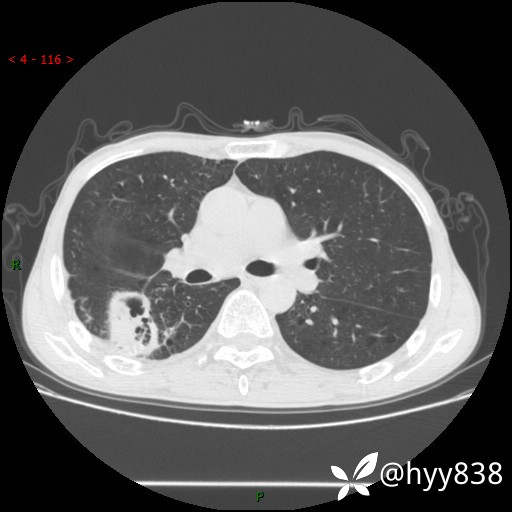

老年男性,肺团片状占位+体重下降,肿瘤 VS 真菌 VS 细菌,看看你的意见--结果公布~

简要病史:患者7天前无明显诱因出现咳嗽咳痰,咳绿色、褐色痰,吸烟后加重,伴心慌、胸闷,无畏寒发热,无头晕头痛,无鼻塞流涕,无痰中带血及咯血,无胸痛、呼吸困难,无全身酸痛,为求进一步诊治于我院就诊,门诊完善胸部CT提示“右下肺团片状影,考虑肿瘤?感染?”,门诊以“咳嗽待查”收住入院。 起病以来,患者精神、饮食、睡眠尚可,大、小便正常,体力下降,体重下降8斤。空腹血糖:6.42mmol/L。

辅助检查:CT

临床诊断:肿瘤?感染?

增强动脉期